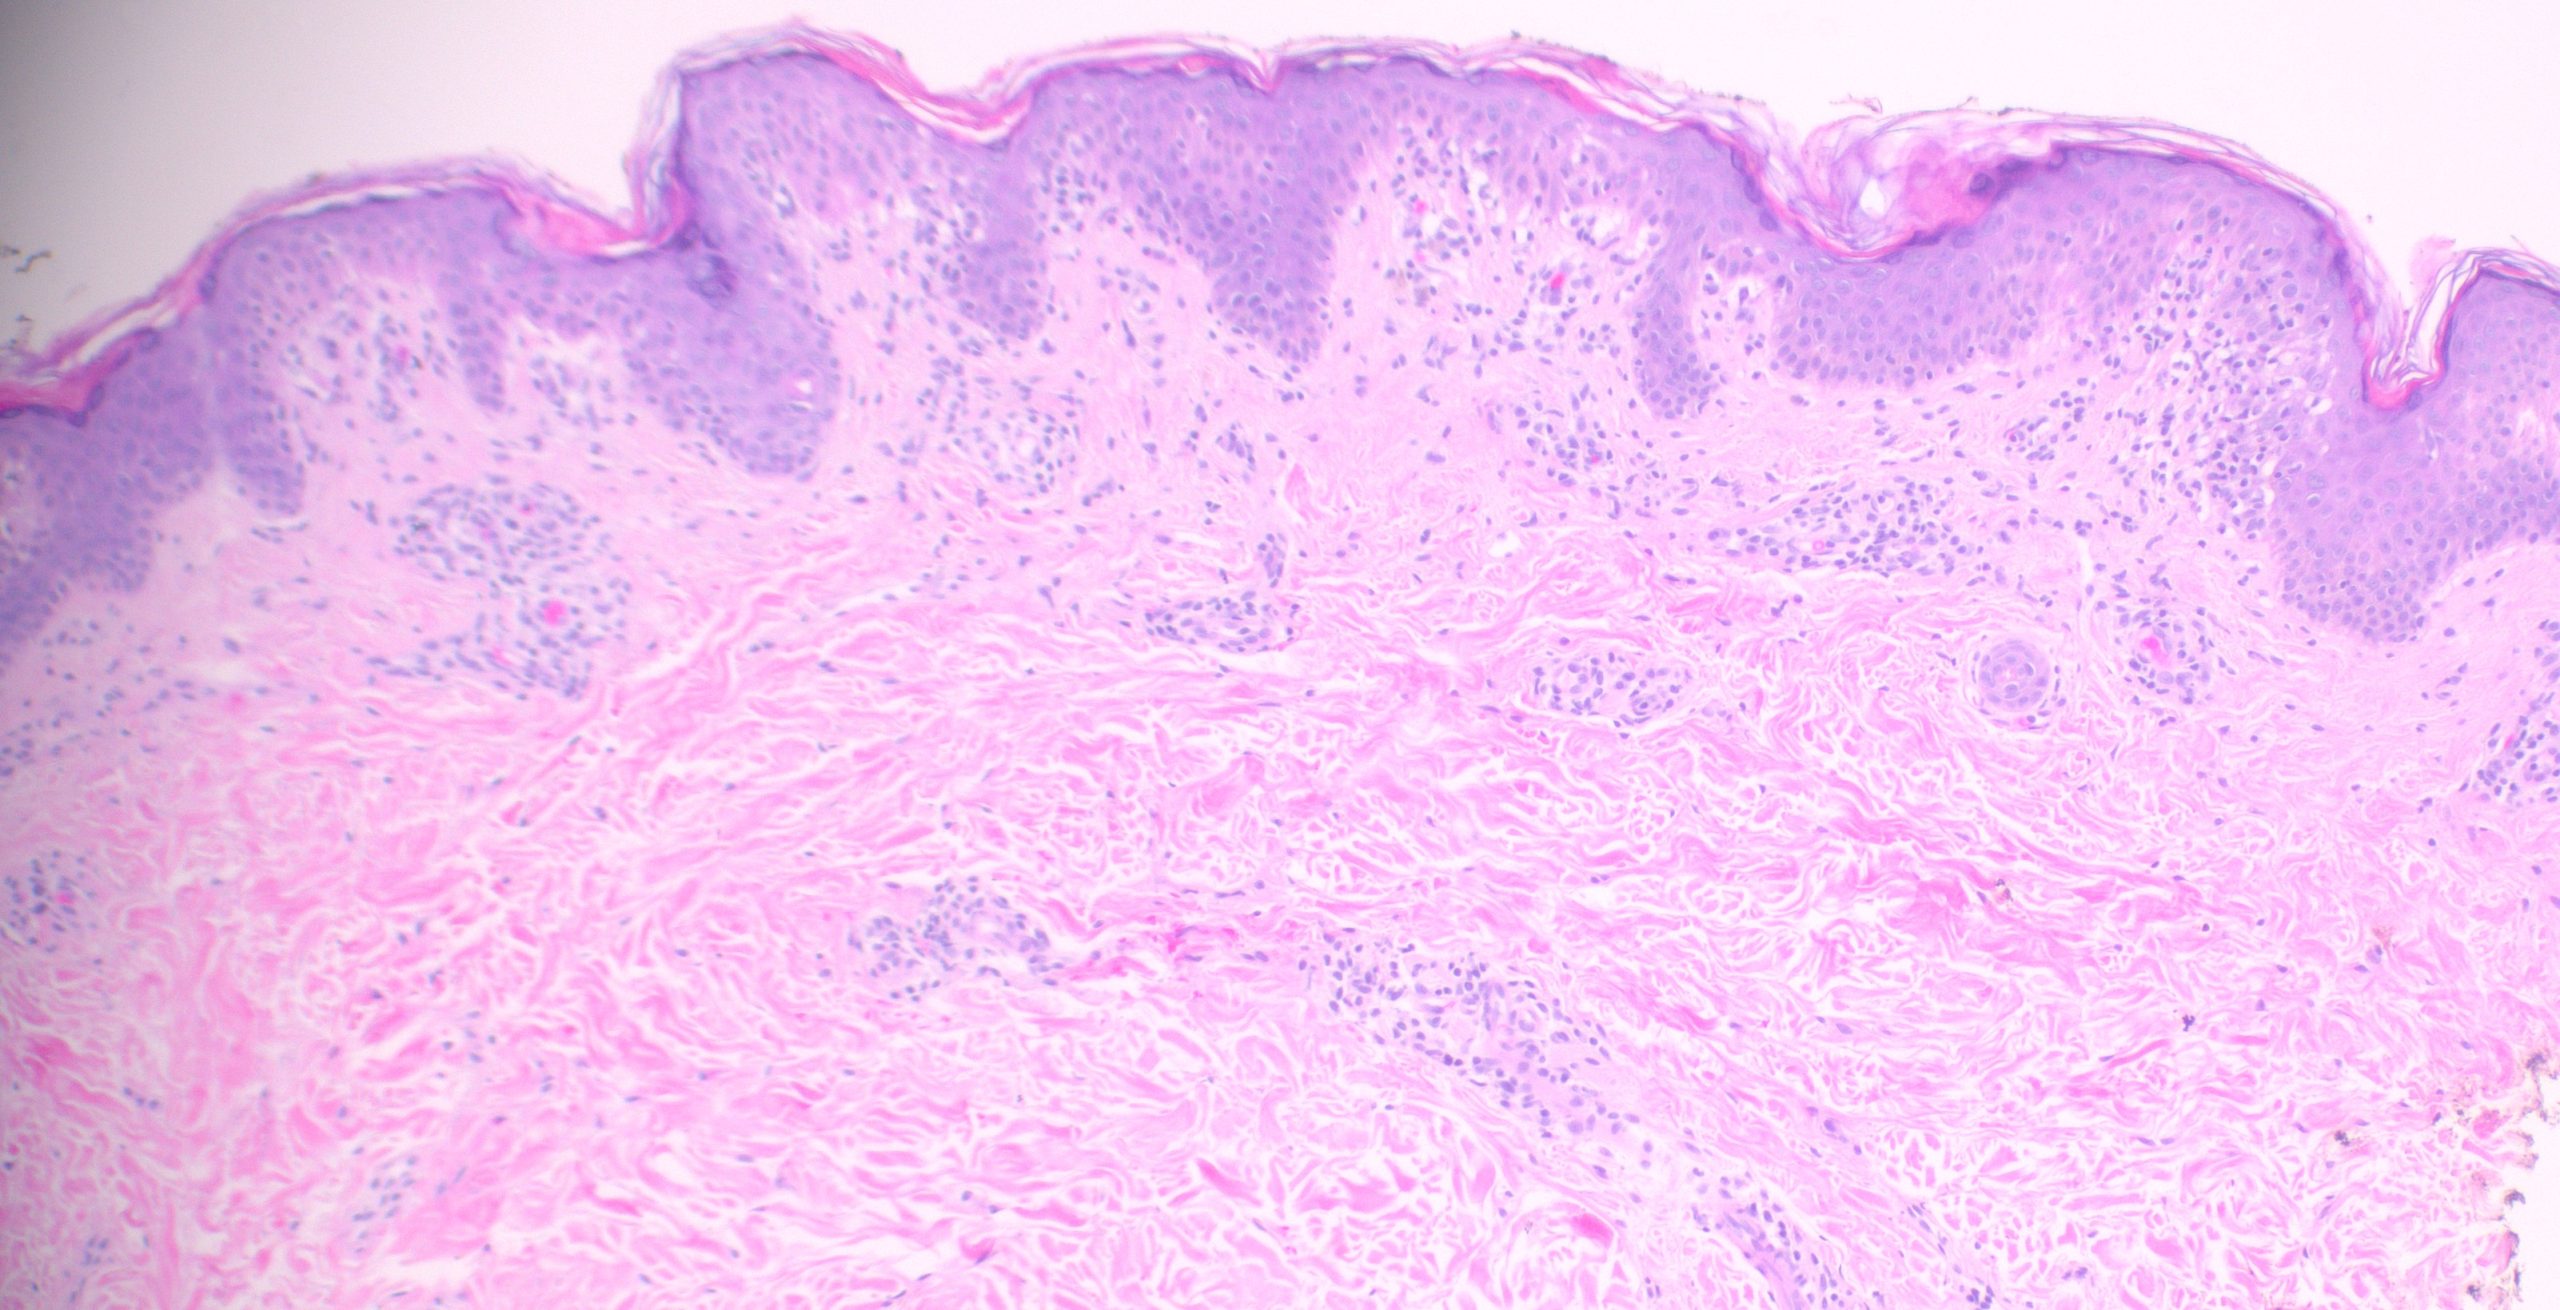

(Low-power histologic view of diffuse rash biopsy)

Pityriasis Lichenoides et Varioliformis Acute (PLEVA)

The combination of a wedge-shaped perivascular lymphocytic infiltrate, necrotic keratinocytes in the epidermis with overlying parakeratosis, and erythrocyte extravasation into the epidermis and superficial dermis is diagnostic of PLEVA. This triad, together with the clinical picture of a young patient with a diffuse papular rash on the trunk, clinches the diagnosis. PLEVA commonly affects patients under 30 years of age, with lesions involving the trunk and proximal extremities presenting as red-brown, mildly pruritic papules that may form blisters, crusts, or ulcers.